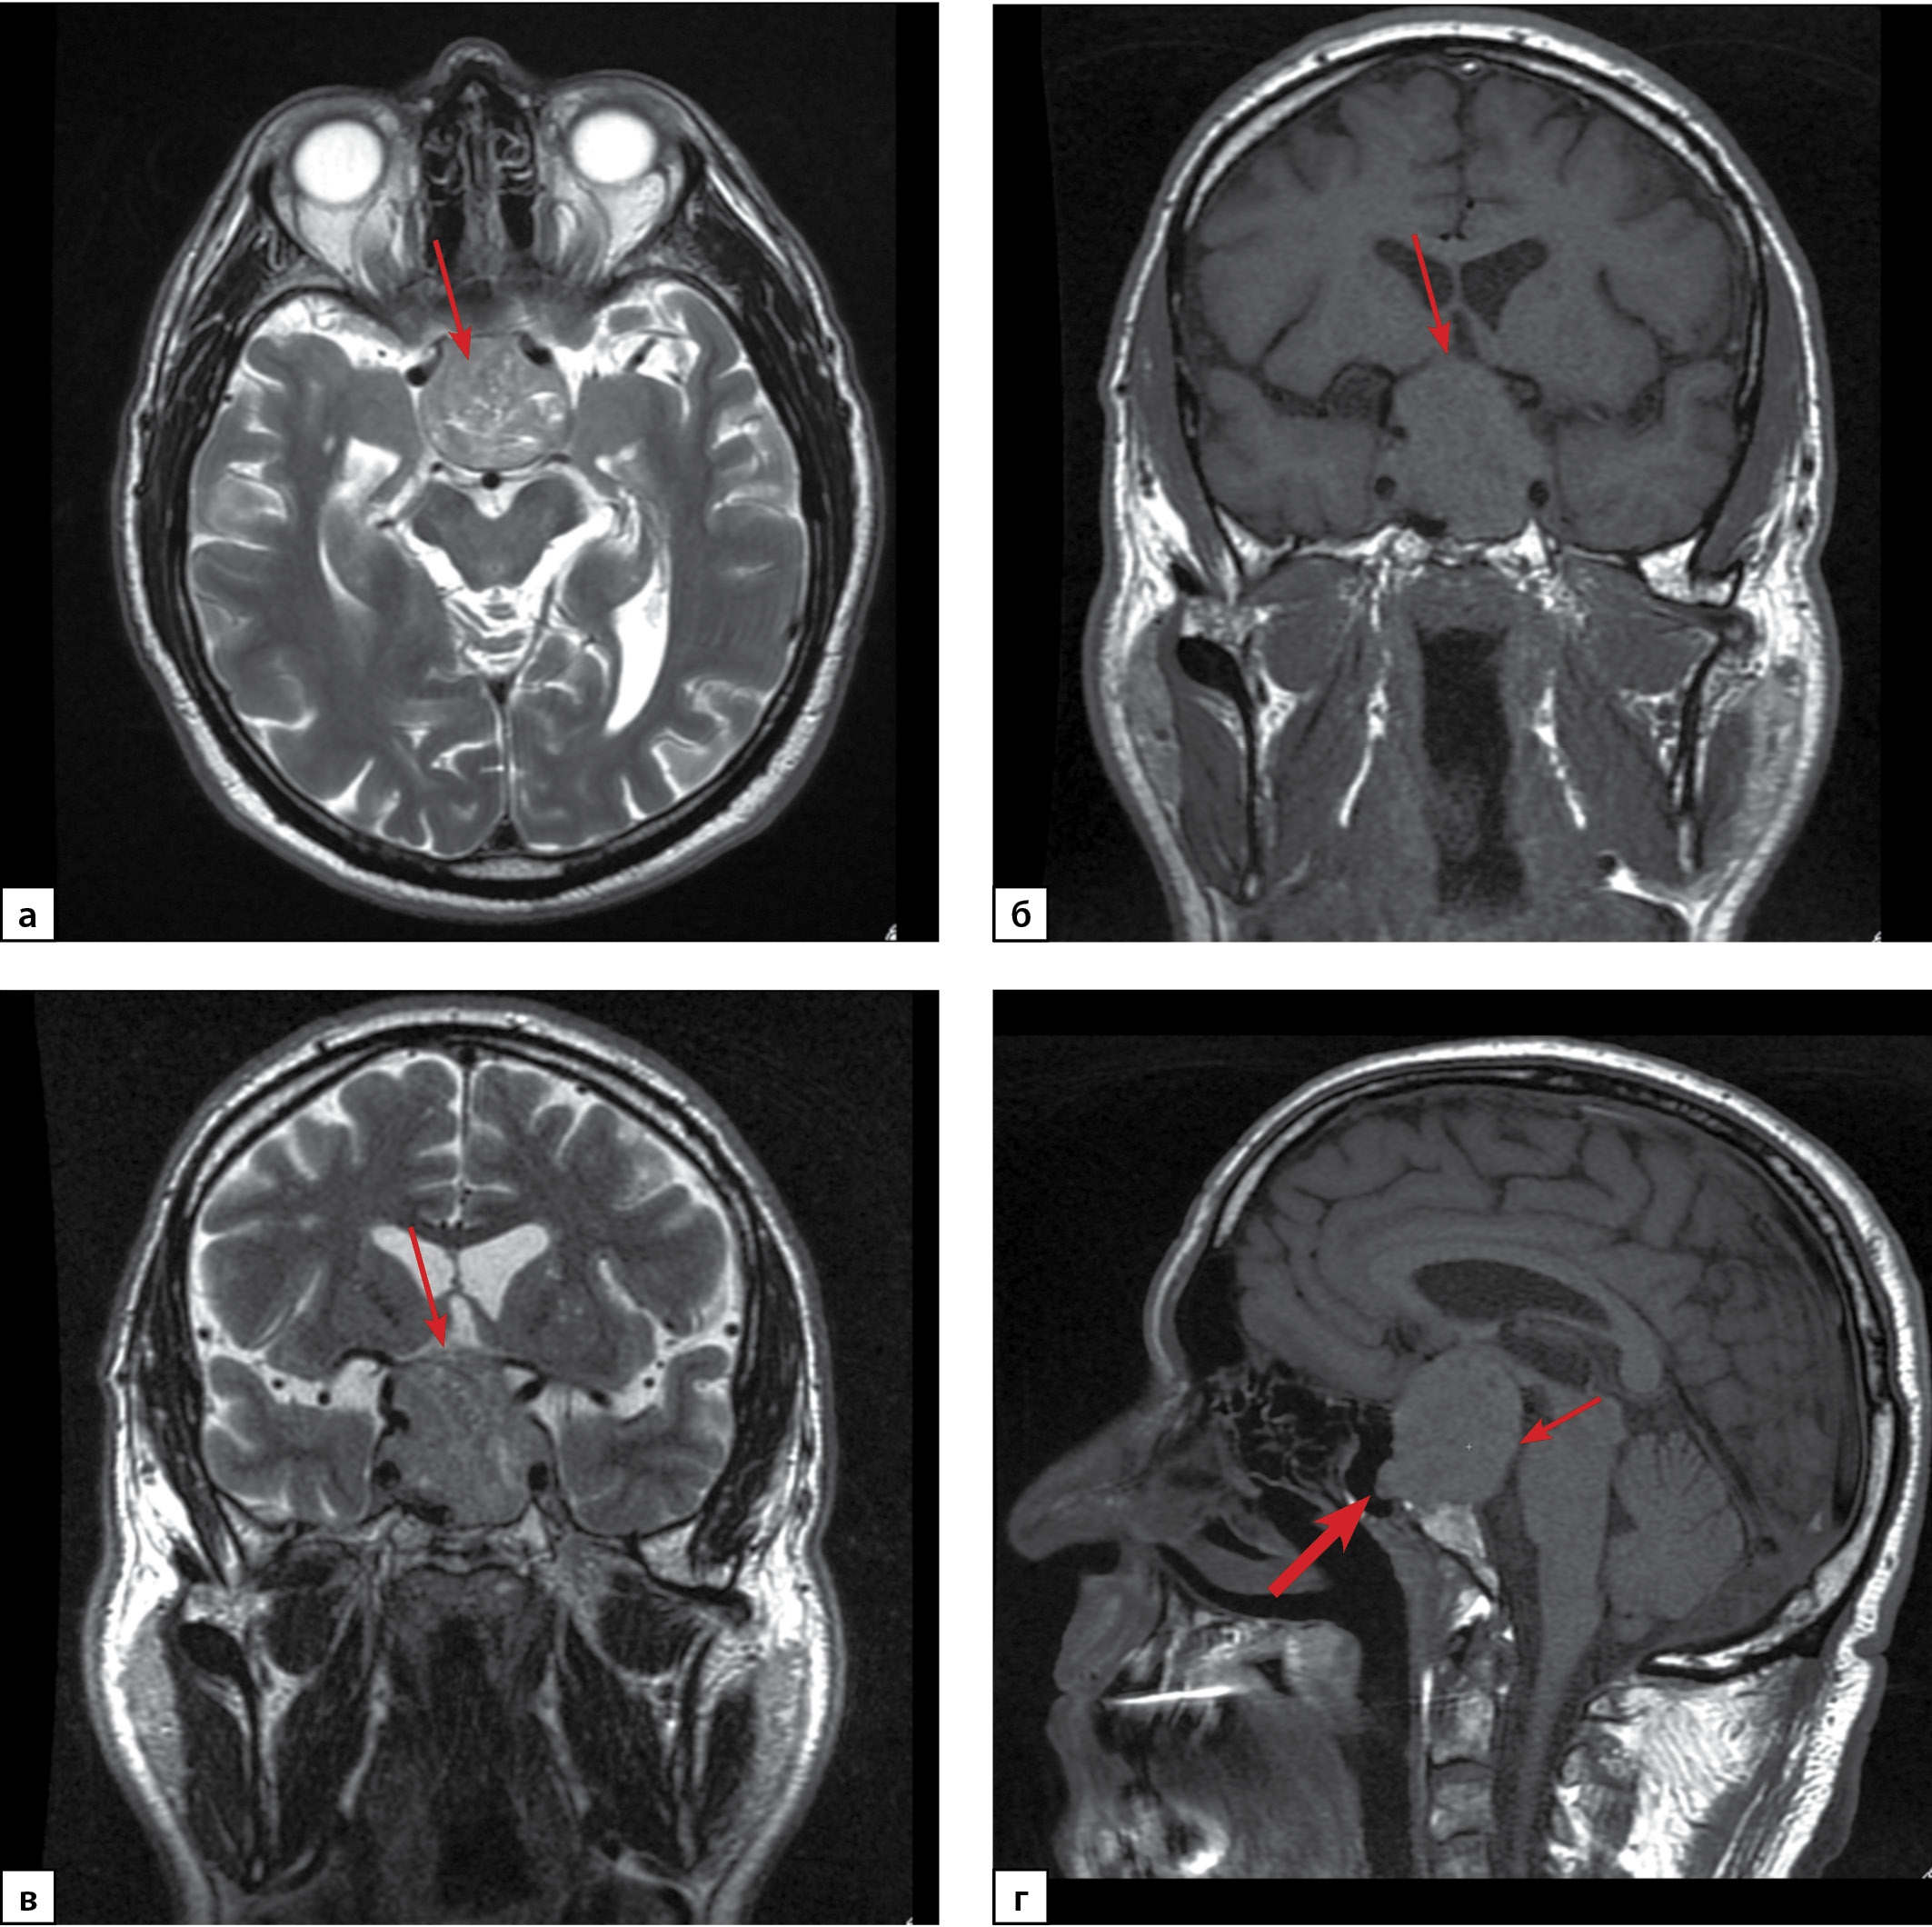

Гормонально-активные гонадотропиномы — это редкие опухоли гипофиза, секретирующие один или два гонадотропных гормона (фолликулостимулирующий гормон (ФСГ) и/или лютеинизирующий гормон (ЛГ)), которые обладают биологической активностью. В большинстве случаев гонадотропиномы являются «молчащими» и составляют более половины гормонально-неактивных аденом гипофиза. В статье представлено описание редкого клинического наблюдения: ЛГ/ФСГ-секретирующей макроаденомы гипофиза с развитием битемпоральной гемианопсии у 62-летнего мужчины. Пациенту была проведена трансназальная транссфеноидальная аденомэктомия, позволившая достичь ремиссии заболевания. Отличительной особенностью данного случая являлось наличие вторичного эритроцитоза, развившегося вследствие эндогенной гиперандрогении, что потребовало проведения процедур эксфузий крови с целью нормализации уровня гематокрита перед проведением оперативного вмешательства. Примечательно, что клинические признаки эритроцитоза у пациента были выявлены задолго до развития зрительных нарушений. Представленный клинический случай демонстрирует сложность ранней диагностики гормонально-активных гонадотропином.